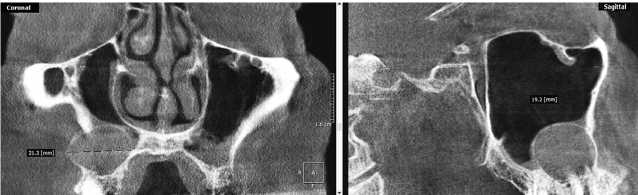

Верхнечелюстная киста слева

Верхнечелюстная киста слева 112 фотографий